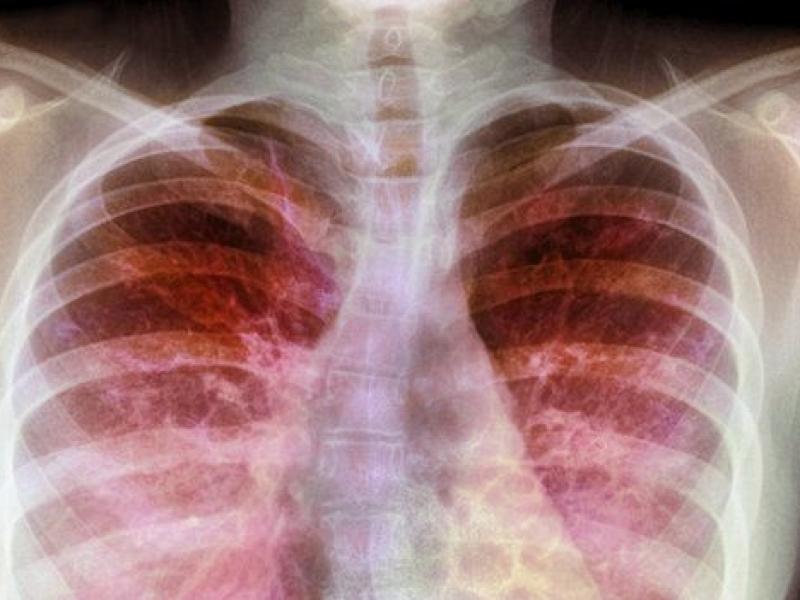

Kistik fibroz, akciğerleri ve sindirim sistemini etkileyen kalıtsal bir hastalıktır. Vücut, ciğerleri tıkayabilecek ve pankreasını tıkayabilecek kalın ve yapışkan mukus üretir.

Kistik fibroz, esas olarak akciğerleri ve sindirim sistemini etkileyen genetik bir hastalıktır, ancak karaciğer hastalığı ve diyabet gibi ölümcül komplikasyonlara neden olabilir.

Kistik fibroz sorumlu olan kusurlu gen, normalden daha kalın, daha yapışkan mukus oluşumuna neden olur. Bu mukusun akciğerlerden öksürülmesi zordur. Bu nefes almayı zorlaştırabilir ve ciddi akciğer enfeksiyonlarına neden olabilir.

Kistik fibrozun akciğerleri tıkaması, bronşit ve zatürree gibi akciğer enfeksiyonları riskini arttırır, çünkü patojenlerin büyümesi için en uygun koşulları yaratır.

Kistik fibrozlu kişilerin temiz nefes almasını sağlamak ve akciğer enfeksiyonlarını en aza indirmek için akciğerlerinden mukustan kurtulmaları çok önemlidir.